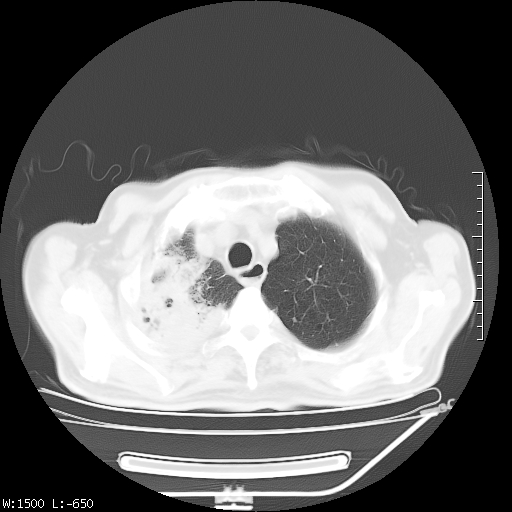

标题: CT23994:男、72、咳嗽、气短两月余,近来消瘦。 [打印本页]

标题: CT23994:男、72、咳嗽、气短两月余,近来消瘦。

tb可能性大(双肺均可见片状密度增高灶,其内可见低密度空洞)。

右上肺大片状密度增高影,与胸膜关系密切,内见低密度透亮影,胸膜下可见三角形不张影,左下肺沿支气管走形结节影,纵膈内淋巴结显示。考虑结核并疤痕性不张可能性大,建议穿刺活检,排除肺泡癌。